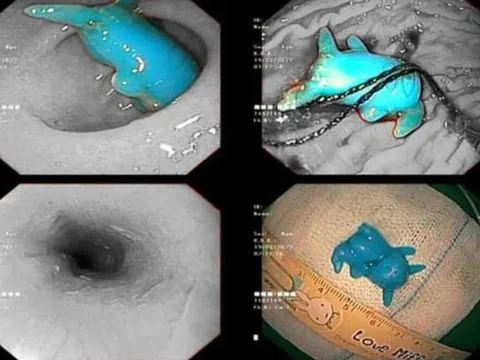

Đồ chơi Pikachu kẹt trong thực quản bé trai 6 tuổi

Dị vật được lấy ra từ thực quản bé trai 6 tuổi là món đồ chơi pikachu bằng nhựa, có kích thước 2x2,5x1 cm.